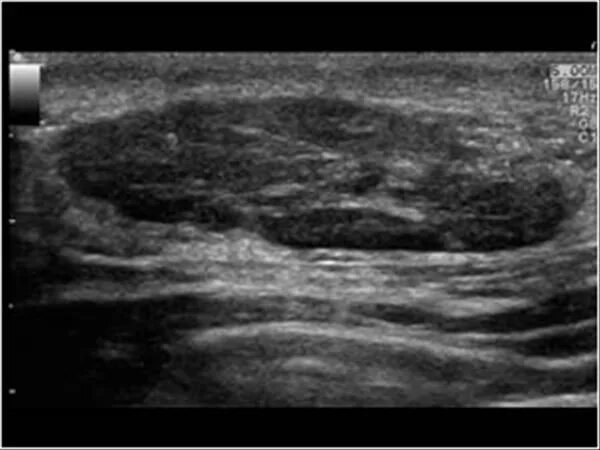

Фиброматоз мягких